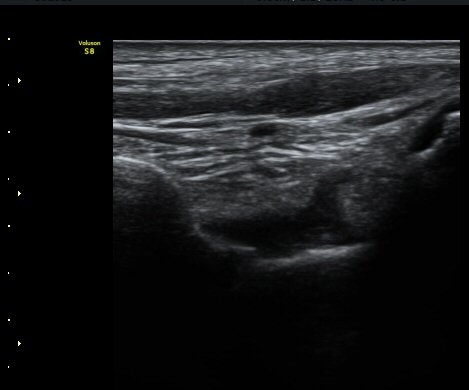

¹ß¸ñ ¾Õ Á¾´Ü¸é°Ë»ç¿¡¼­ ¹ß¸ñ°üÀý ³» ¼ö¾×Àú·ù°¡ °üÂûµÈ´Ù(±×¸² 1).